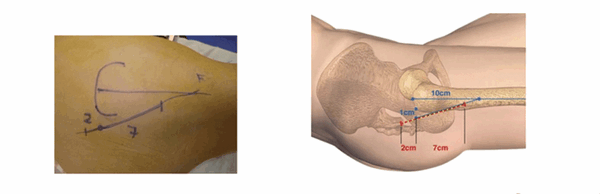

Нанесение маркеров для выполнения разреза. (Graphique de l’incision)

Нанесение ориентиров упрощает выполнение разреза. Верхний бугор большого вертела хорошо пальпируется, когда пациент находится в положении лежа на боку на плоской поверхности. От этого места наносятся две точки: первая на расстоянии 1 см располагается за бугром большого вертела, вторая — на расстоянии 10 см от вершины по оси бедренной кости. По линии, связывающей эти две точки делается разрез: 2 см ниже и 7 см выше от бугра вертела.

Начало операции, разрез поверхности. (L’abord superficiel)